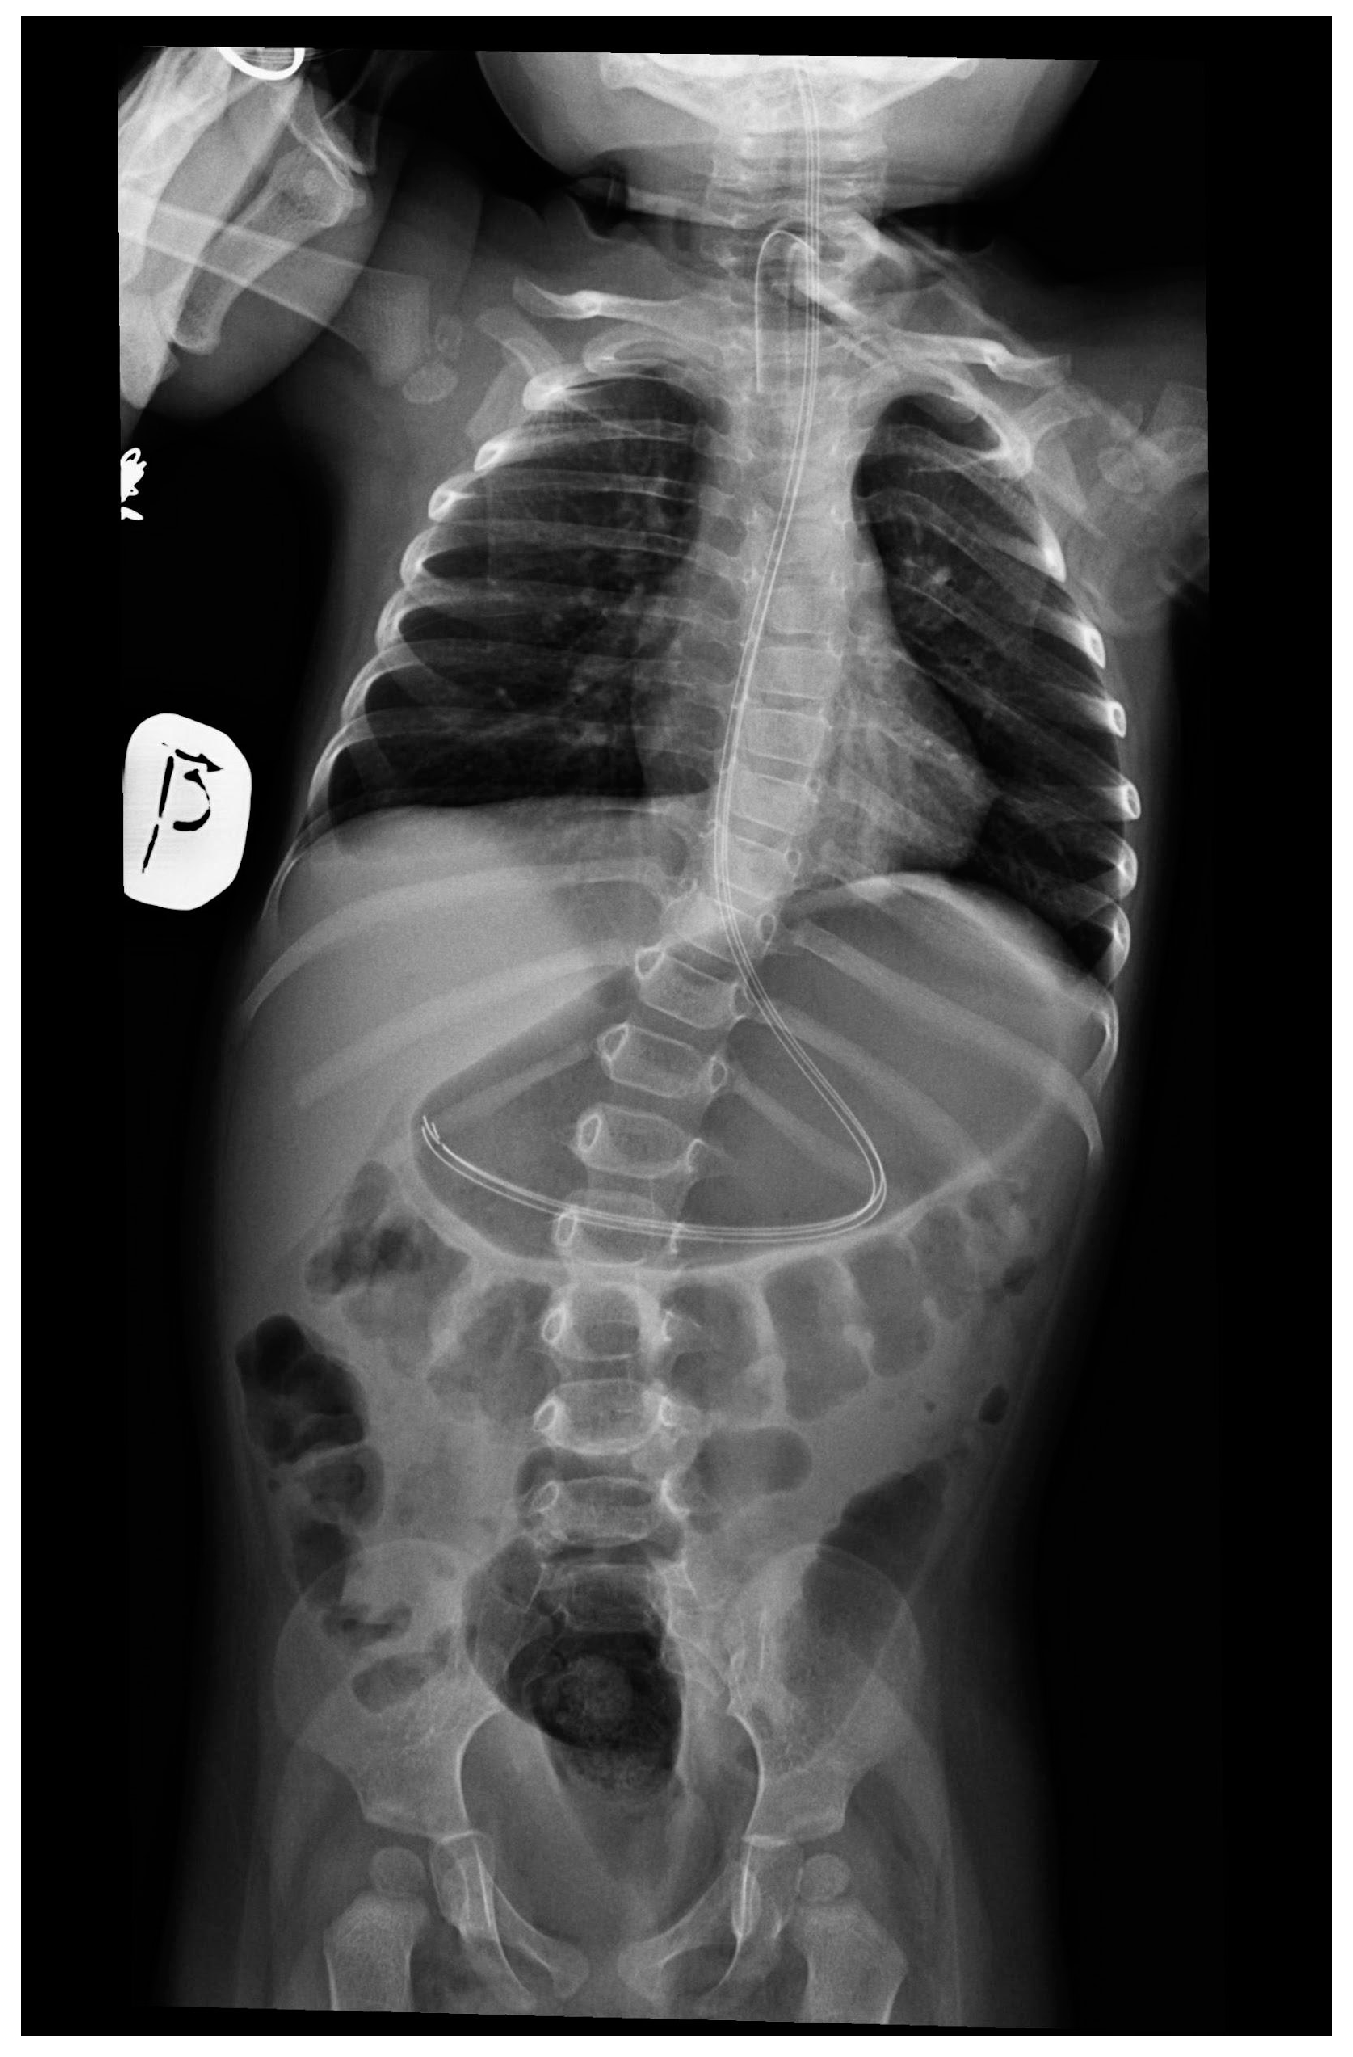

At 13 months, she required hospitalization to optimize nutritional management. Before admission, the girl was continuously fed via an intra-gastric tube and was experiencing increasing feeding difficulties, including frequent vomiting, regurgitation, and delayed gastric emptying (with 20–30 mL retention). Chronic constipation, intermittent tachycardia, and increased sweating were also reported. Upon physical examination, the girl was in a stable general condition, on ventilation via tracheostomy, and fed via a G-tube, with markedly reduced muscle tone, predominantly in the lower limbs. Moreover, the abnormal positioning of the right upper limb with internal rotation, varus foot positioning, left-sided scoliosis, and hands with visible atrophy of the small metacarpal muscles and accumulation of fatty tissue within the proximal phalanges (fatty pads) were noted. She was diagnosed with gastroparesis, which, together with existing feeding difficulties, led to the placement of a percutaneous endoscopic gastrostomy (PEG) (Figure 1). At the same time, subclinical hypothyroidism was diagnosed, and levothyroxine treatment was initiated.

Figure 1. Features of gastroparesis and scoliosis in patient no. 1 at 13 months.